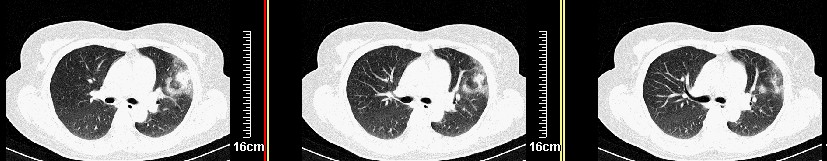

一周之后 复查结果 5mm扫描 40多岁 我们医院的护士

左肺上叶肿块,肺窗周围有“晕征”,纵隔窗有毛刺,临床资料???只能考虑占位???

病灶分明小多多了